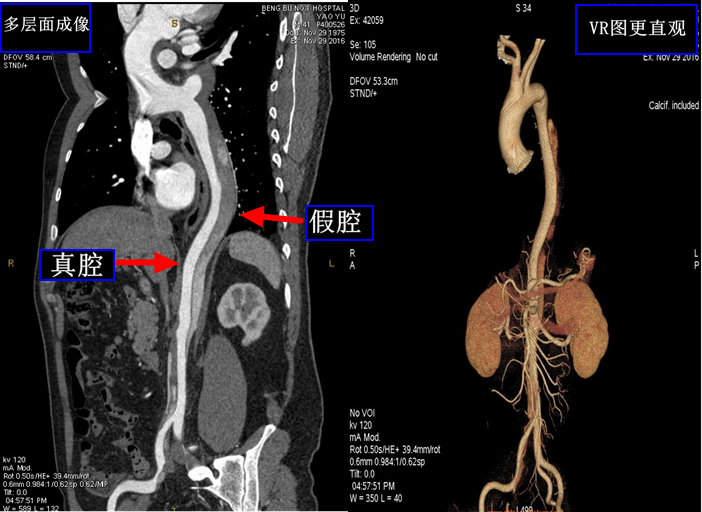

CT检查对中枢神经系统疾病、头颈部疾病的诊断、大血管检查等也有很大的价值。如:急性脑出血、主动脉瘤动脉夹层、冠心病、肺动脉栓塞等急重症的检查尤为重要。(如下图为主动脉夹层CTA检查,能清晰显示主动脉血管的真腔和假腔情况)

乳腺dr能检查什么【科普】DR、CT、MR?放射科检查项目选哪个好?_https://www.jmylbn.com_新闻资讯_第3张